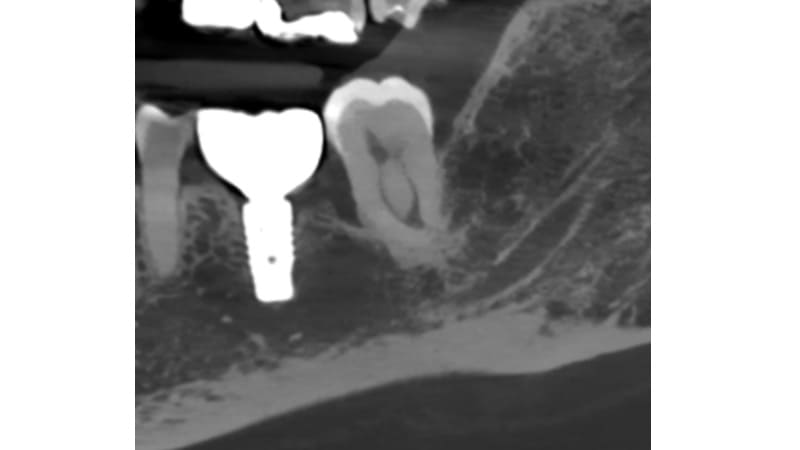

症例④:奥歯が違和感がある

| 治療科目 | 歯周組織再生療法 |

|---|---|

| 主訴 | 奥歯が違和感がある |

| 治療期間 | 1年 |

| 治療費 | 220,000円 |

| 治療内容 | 抜髄後、エムドゲインとバイオスを使い再生療法を行った。 |

| 治療のリスク | 角化歯肉の状態により再度感染を起こす可能性があり、遊離歯肉移植の併用が必要なこともあります。清掃方法によって再感染する可能性があり、定期的な通院でチェックしていく必要があります。 |